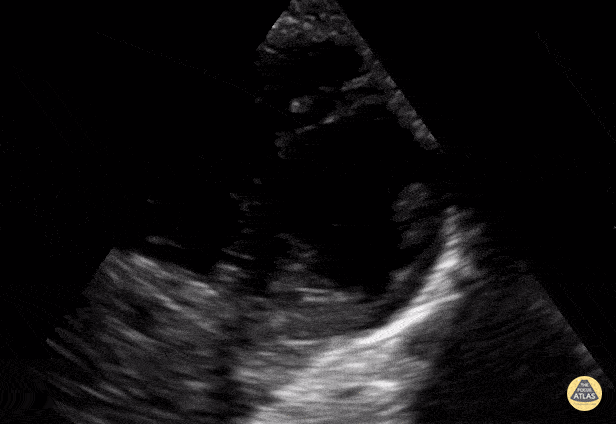

Normal PSSA apex in a 9-year-old. Contributor: Jaron Smith, MD, Phoenix Children's Hospital

View: Unspecified Parasternal Long Axis Parasternal Short Axis Apical Four-Chamber Subcostal Four-Chamber Subcostal Inferior Vena Cava Right Upper Quadrant Left Upper Quadrant Suprapubic Longitudinal Suprapubic Transverse Subxiphoid Anterior Thoracic Phrenic